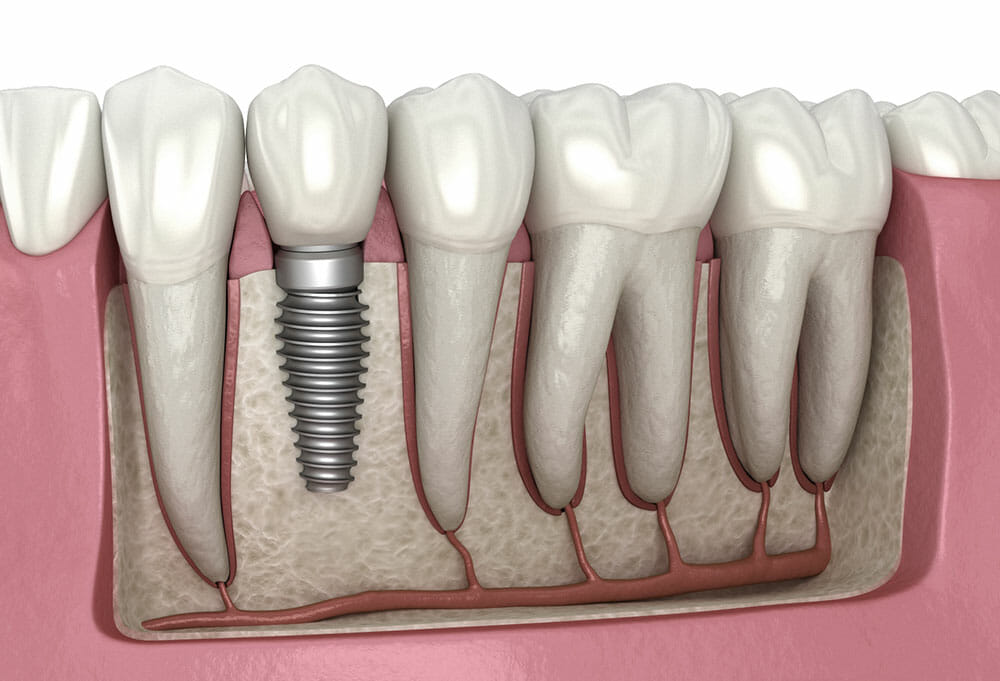

Dental implants are artificial tooth roots that provide a permanent base for replacement teeth. They are an excellent option for people who have lost one or more natural teeth due to injury, decay, or some other reason. Implants offer a natural-looking and long-lasting solution that can improve oral health and restore confidence in your smile.

The implant itself is made of titanium and is surgically placed into the jawbone where it fuses with the bone over time. This creates a strong foundation for the replacement tooth or bridge, which is attached to the implant using an abutment.

Dental implants are an essential and permanent solution for missing teeth. They’re made of titanium or other materials that are compatible with the human body, so they can fuse with your jawbone and provide a stable base for the replacement tooth.

Endosteal implants are placed directly into the jawbone, whereas subperiosteal implants are placed under the gum but on or above the jawbone.Endosteal implants come in various shapes and sizes to fit different patients’ needs. The most common form is screw-shaped, which is implanted directly into your jawbone through surgery.

Subperiosteal dental implants consist of a metal frame that’s fitted onto your jawbone just beneath your gums. Posts protrude from this frame through which replacement teeth will be attached.